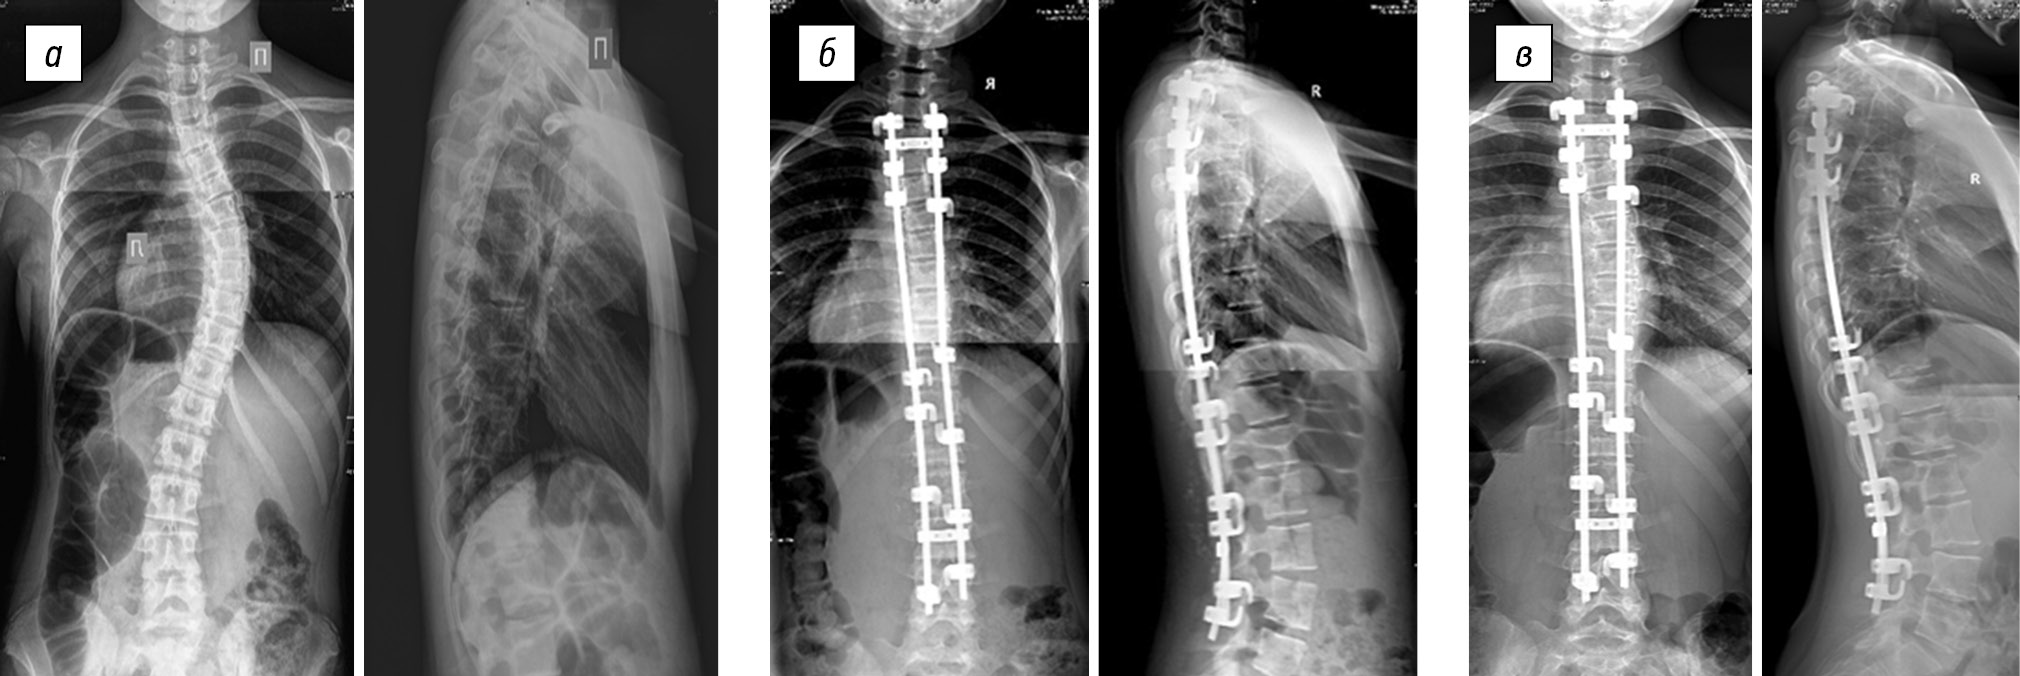

In group 5 (Table 5), the average preoperative size of the thoracic scoliotic curve was 82.8 ± 22.6°, and the postoperative main scoliotic curve decreased to 31.2 ± 18.5° (p < 0.05), that is, the value of the primary correction was 51.6 ± 13.6°, which was found in 64.4 ± 14.6% of the cases (p < 0.05). Postoperative progression was on average 7.1 ± 7.5°, which was found in 15.0 ± 16.5% of the cases (Fig. 5). The average patient age was 12.4 ± 1.0 years, and the average duration of postoperative follow-up was 99.6 ± 29.3 months.

Fig. 5. Radiographs of a 13-year-old female patient in two views: a — preoperative image of degree IV right-sided thoracic scoliotic deformity (51° according to Cobb) with lumbar anti-curvature (49°), thoracic kyphosis of 62°, and lumbar lordosis of 59°; b — surgical correction of scoliotic deformity of the spine using laminar fixation in combination with mobilizing discectomy at the levels of Th5–Th6, Th6–Th7, Th7–Th8, and Th8–Th9 results in main thoracic curve of 24°, lumbar anti-curvature of 20°, thoracic kyphosis of 40°, and lumbar lordosis of 46°; c — X-ray control 6 years after surgery revealed the main thoracic curve of 35°, lumbar anti-curvature of 34°, thoracic kyphosis of 51°, and lumbar lordosis of 57°